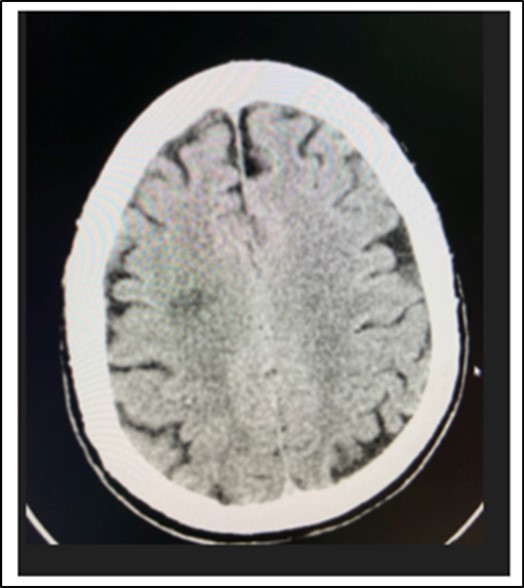

At the emergency room of the tertiary hospital, the patient had persistence of the diplopia and dizziness. The initial impression at that time was Cerebrovascular Infarct, thus a Plain Cranial CT Scan was done (conducted 6 hours after the onset of symptoms), which revealed a hypodense focus in the sub-cortical region of the right centrum semiovale extending to the right corona radiata, orbits, midbrain and pons were all normal. (Figure 2 and Figure 3)

Figure 4.Cranial CT Scan plain, axial of the patient done 6 hours after onset of diplopia, shows a hypodense focus in the sub cortical region of the right centrum semiovale extending to the right corona radiata